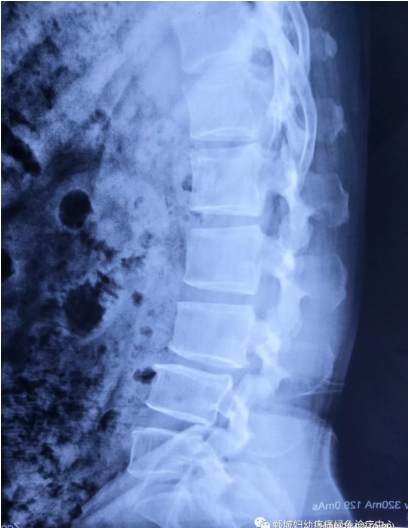

不经意间听到有人说医院疼痛科可以不吃药不打针,用无痛苦、无创伤的方法治疗腰痛。陈女士就抱着试试看的心理来到了郸城县妇幼保健院疼痛科,疼痛科时庆祥主任详细了解病情,结合腰椎磁共振及体征后告诉陈女士她不用手术,通过腰椎脊柱定位周期减压牵引系统(外星舱)也能解决腰痛、腰椎滑脱、腰椎反弓这些问题。陈女士未曾想到经过十五天的治疗后腰部及下肢放射性疼痛症状基本消失。陈女士感到十分激动与感谢,就在当地卫生院做了一个腰椎正侧位x片和之前的片子作对比,发现腰椎滑脱明显改善。她说道:感谢郸城县妇幼保健院疼痛科的所有医护人员、感谢外星舱脊柱减压治好了我的腰痛,也感谢告诉我来这里的人,她的一句话,让我省了好几万元的手术费!

治疗后